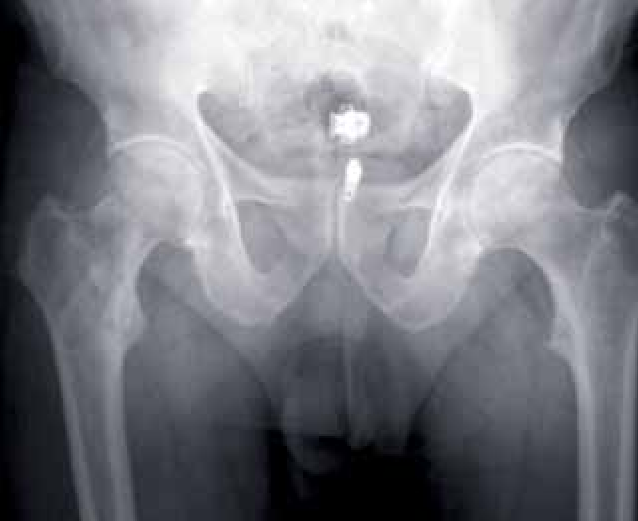

The tumor can occur in both male and female genders equally, usually in the later ages of life. The initial clue to diagnosing liposclerosing myxofibrous tumor is the presence of proximal femur in patients, which is found during the radiographic examination. There are multiple patterns of this tumor observed under the microscope.

A radiographic exam holds prime importance in the prognosis of the fibro-osseous tumor. There are a variety of histological features associated with the tumor that makes it daunting to distinguish between other osseous tumors.